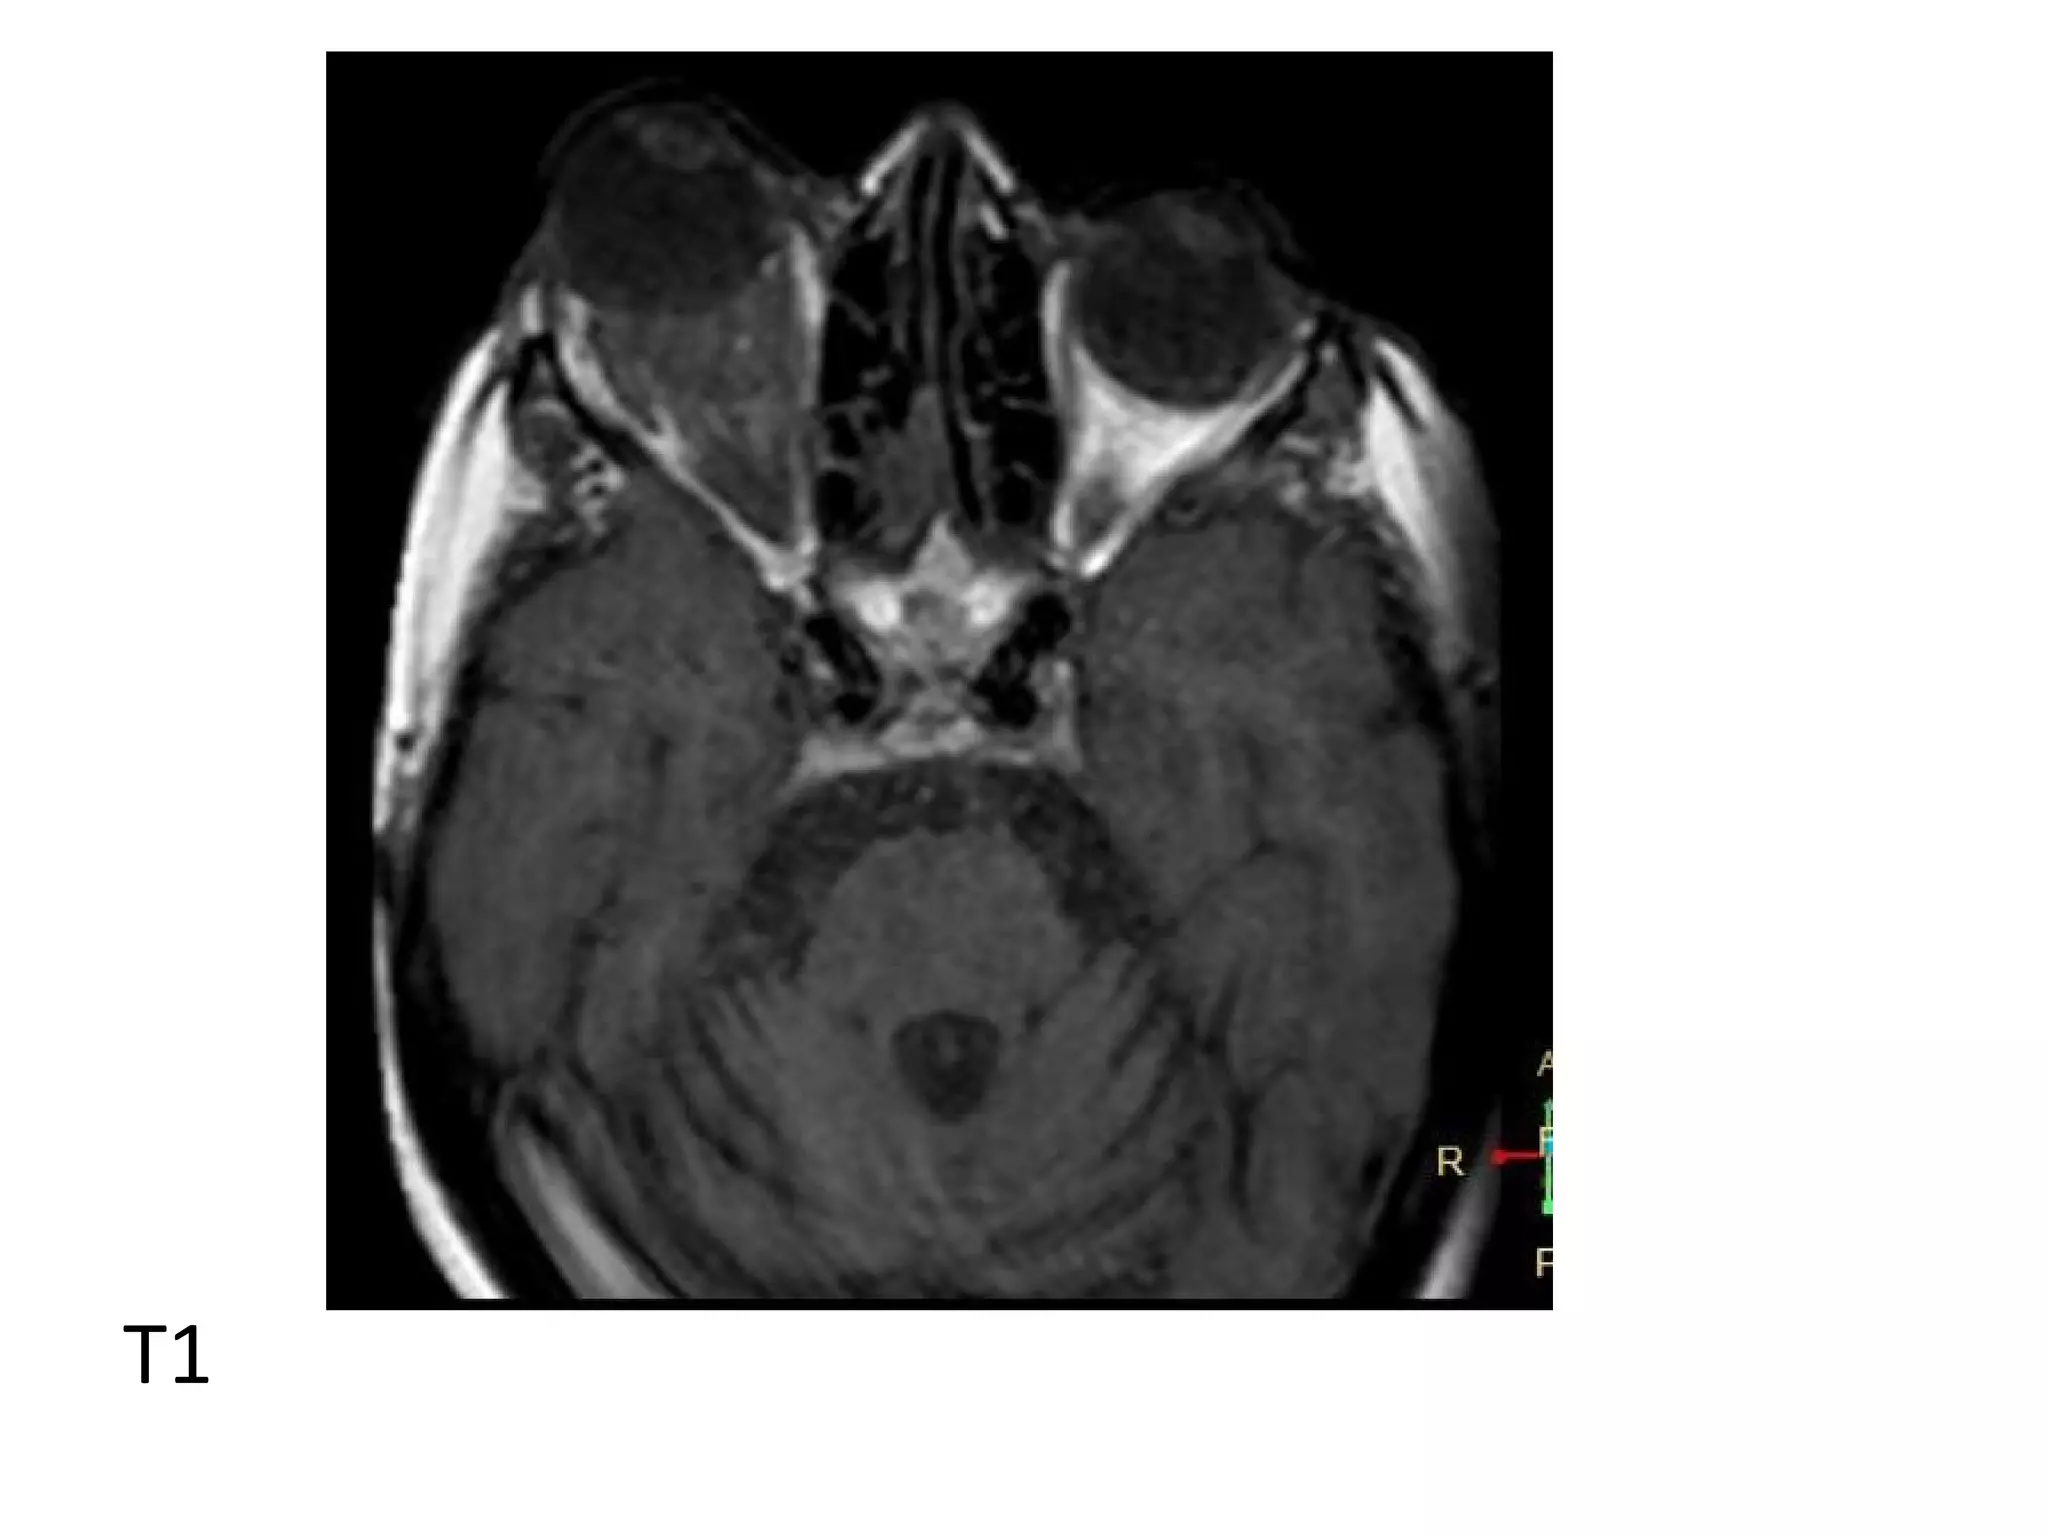

T1

T2

T1+C

2-MRI :

*T1 : The tumor is slightly/moderately

hyperintense

*T2 : Moderately low intensity

*T1+C : The tumor enhances